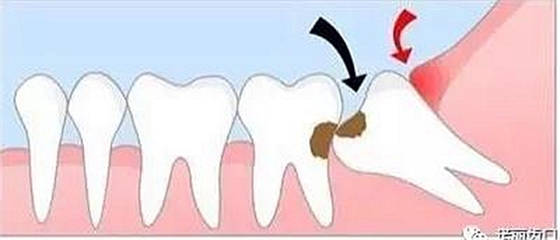

造成鄰牙病變

如果生長(zhǎng)空間不足,智齒會(huì)使勁兒頂住相鄰的牙齒繼續(xù)生長(zhǎng),可能導(dǎo)致兩顆牙齒都保不住,此時(shí)建議拔除。